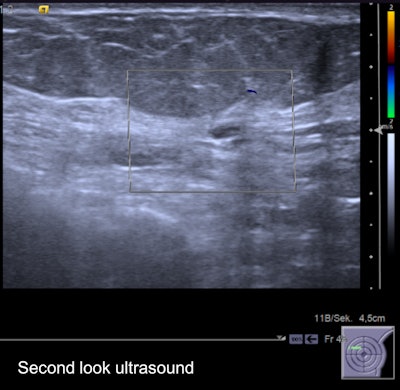

Second-look ultrasound of the lesion. It's an oval, horizontally oriented lesion with circumscribed borders, posterior acoustic enhancement, and no hypervascularization. Internal features unspecific hypoisoechoic. It was found to be probably benign on ultrasound, and followed up over two years without evidence of growth."We all do a lot of examinations; most of them we do not immediately get feedback from," he said. "I heard doctors from the German screening program brag, calling their sensitivity 100% -- that is of course they see the cancers they detect, not the ones they miss. Regarding second-look ultrasound, it is similar and a lot of things can be taught: How often do I find a correlate for MRI lesions? Can I also see nonmass lesions? Can I upgrade or downgrade lesions using ultrasound? What lesions am I likely to miss and can I do anything about it?"